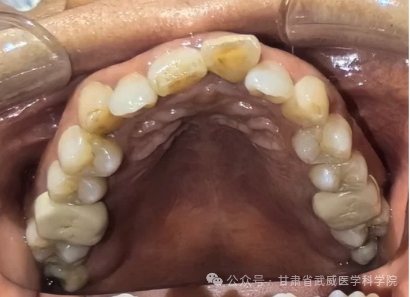

牙列不齐,医学上称为“错颌畸形”,是指儿童在生长发育过程中,由先天的遗传因素或后天的环境因素(如疾病、口腔不良习惯、替牙异常等)导致的牙齿、颌骨、颅面的畸形。

·清洁死角多: 牙齿重叠交错,容易藏匿食物残渣和牙菌斑,刷牙刷不干净。

·引发牙病: 极易导致龋齿(蛀牙)、牙龈炎、牙周病(牙龈红肿、出血、萎缩)。

·替牙障碍: 乳牙过早脱落或迟迟不掉(滞留),导致恒牙萌出位置不够或错位。

·饮食过细: 现代食物太精细,缺乏咀嚼刺激,导致颌骨发育不足,牙齿没地方长。